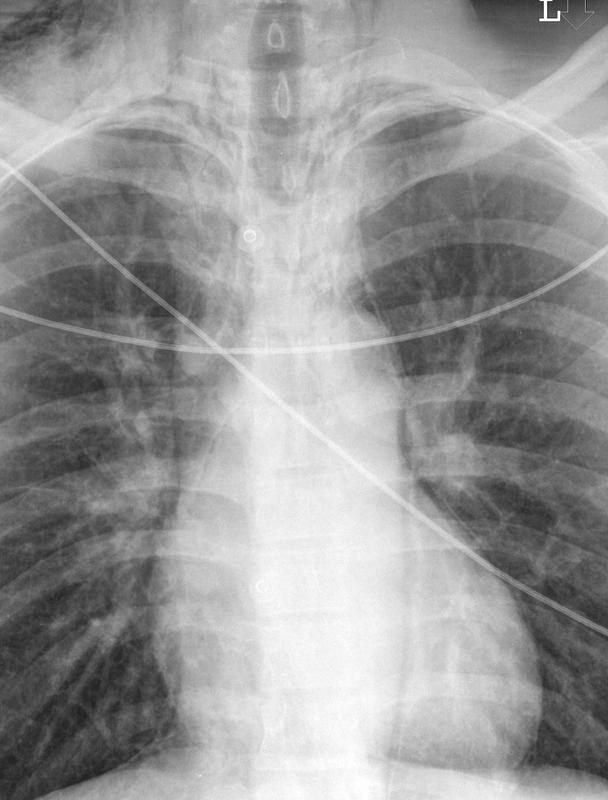

Pneumomediastinum 3